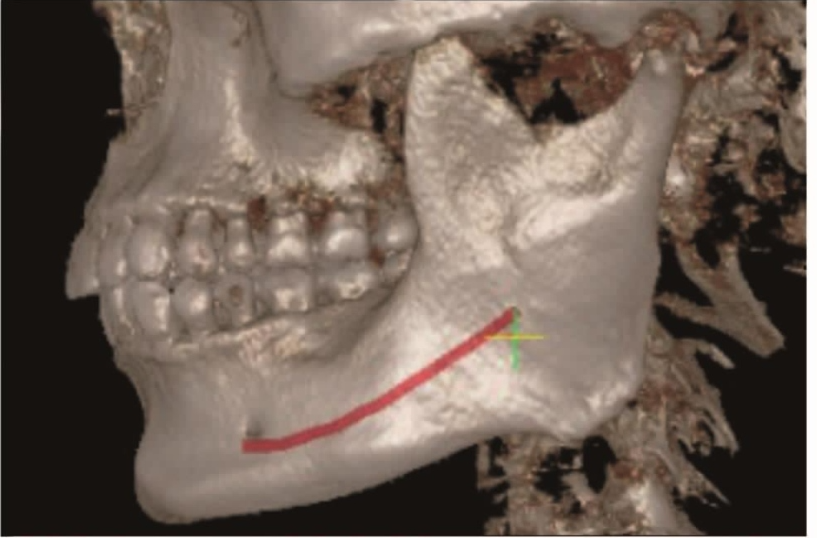

下颌支由喙突、髁突、内、外面四部分组成。下颌骨牙槽突的内侧骨板和外侧骨板都由骨密质构成,骨松质被内外侧骨板包绕其中(图1~3)。

图2 CBCT三维重建图示下颌骨呈蹄铁形,由下颌体和下颌支组成A.侧位图像;B.正位图像